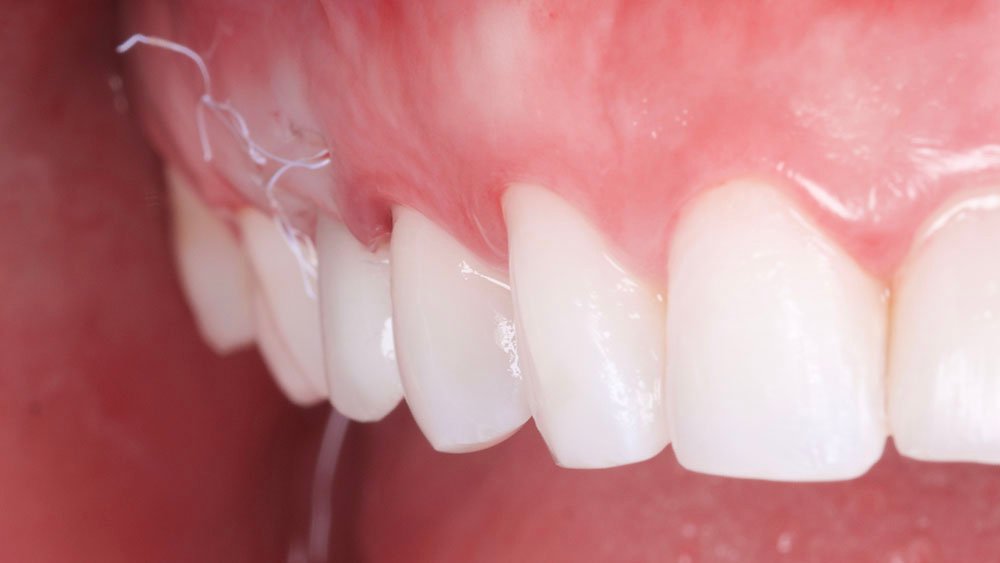

Com auxílio de uma pinça porta agulha Castroviejo e pinça Dietrich 16 (Supremo Instrumentais), e fio de sutura Micro PTFE 5.0 (GolnitTM, Ucrânia-Europa – MICROSUTURE), foi realizado a sutura da região com pontos do tipo colchoeiro horizontal, posicionando o rolo dentro do retalho, tipo envelope na região vestibular.

O procedimento selecionado para esse relato de caso promoveu resultados satisfatórios e melhorou a estética. No término do procedimento cirúrgico, a paciente foi orientada a tomar uma cápsula de Amoxicilina 500 mg (EMS – Germed Farmacêutica, São Paulo- Brasil) a cada 8 horas por sete dias; um comprimido de Nimesulida 100 mg (Eurofarma Laboratórios S/A, São Paulo-Brasil) a cada 12 horas por três dias; e um comprimido de Dipirona 500 mg (Sanofi Medley Farmacêutica Ltda., São Paulo-Brasil) a cada 6 horas. Além disso, foi indicado à paciente que evitasse alimentos pastosos e pegajosos, que preferisse alimentos frios ou gelados e utilizasse bolsa de gelo no local.

No acompanhamento mensal realizou-se proservação e radiografias periapicais da região para verificar a cicatrização dos tecidos e integridade do implante. Após o período de três meses, foi cimentada uma coroa definitiva de zircônia monolítica.